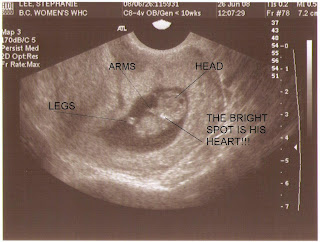

Baby Lee at 9 weeks 2 days:

There you go, a picture of the little guy. Doesn't look much different than the picture of an 8-week ultrasound, except this little guy is mine and so he's GORGEOUS. The best looking in-utero baby in the WORLD! Speaking of the little "guy", Donald and I think we are going to find out the sex after all. Will know by September - I think my detailed ultrasound is September 2. We're still talking about it, but I think we'll go for it.

Here's another picture with notes:

His heart was beating at 171 beats per minute. Didn't hear it, but saw it. He was moving around in there too, very active!